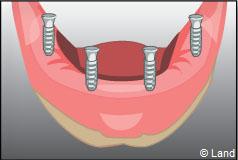

Les implants peuvent aussi servir à stabiliser un appareil amovible au maxillaire supérieur comme au maxillaire inférieur. Dans ce cas, les implants retiennent la prothèse amovible par des systèmes d’attachement.

Deux techniques sont possibles. Elles font appel à la barre de rétention ou aux boutons-pressions.

Exemple d’une réhabilitation complète implantaire